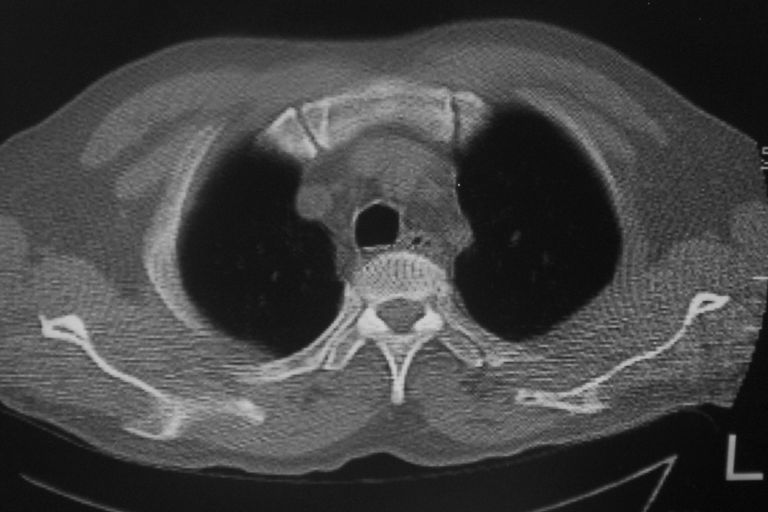

标题: CT10574:男 50岁胸部CT请会诊!

患者 男 50岁 无痛性咯血3天,无其他不适.

左下肺结节状软组织密度影,边缘有毛刺,考虑周围型肺癌。

1 左肺下叶基底段见两结节软组织密度灶, 肺窗边缘见有毛刺征像, 不能排除占位. 2 建议结合临床治疗一周后ct随访在看其结果.

临近胸膜增厚,病变周围肺不清,稍有分叶。结节密度略高,肺、纵隔窗差异不大,肺癌待排。前方还有一个

左下肺结节状软组织密度影,一个边缘有卫星病灶,邻近胸膜增厚.另一个有毛刺.心影周围水样密度影环绕.考虑:

1.肺癌可能.肺tb待排.

2.左侧胸膜增厚.心包积液.